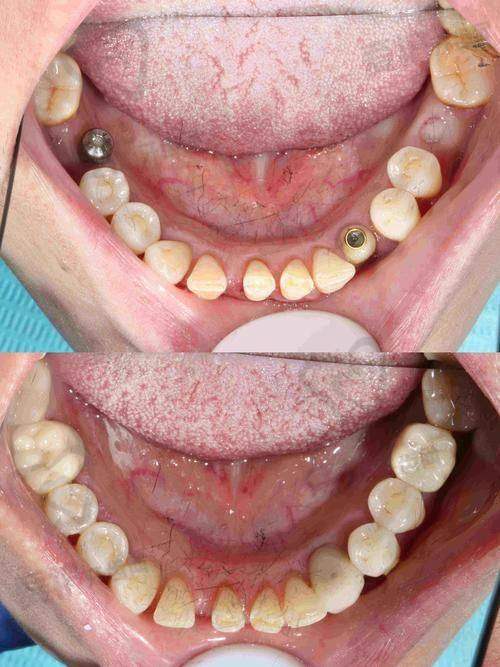

广州曙光美云口腔美国皓圣种植牙的成效如何?

从众多患者的反馈来看,广州曙光美云口腔牟家云医生做的美国皓圣种植牙成效非常好。种植牙的稳定性高,能够像真牙一样正常咀嚼食物,修复了患者的咀嚼功能。而且种植牙的外观与真牙非常相似,几乎可以达到以假乱真的成效,不会影响患者的美观。在长期使用过程中,美国皓圣种植牙的使用寿命也比较长,只要患者注意口腔护理,定期到医院进行复查,种植牙可以陪伴患者特别多年。